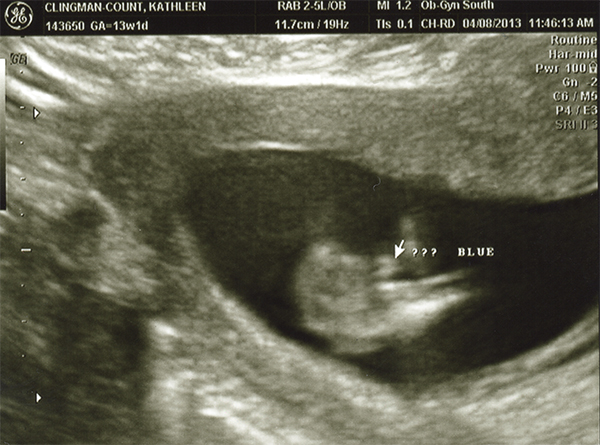

I had an ultrasound on Monday -- 13 weeks. I don't feel as though any of these are very clear pics. Even if they were better, I still wouldn't be any good with ultrasounds! Any of you experts able to make anything out with these? The tech guessed boy but the picture is not clear to me at all! She also kept saying the cord was between baby's legs and that we shouldn't go out and buy anything blue just yet. Any hope that it's a girl??

Attachment 10494